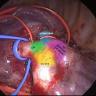

This apical segmentectomy was performed by uniportal approach. Indocyanine green was injected into the blood via a peripheral vein to identify the intersegmental plane, allowing more accurate segmentectomies.